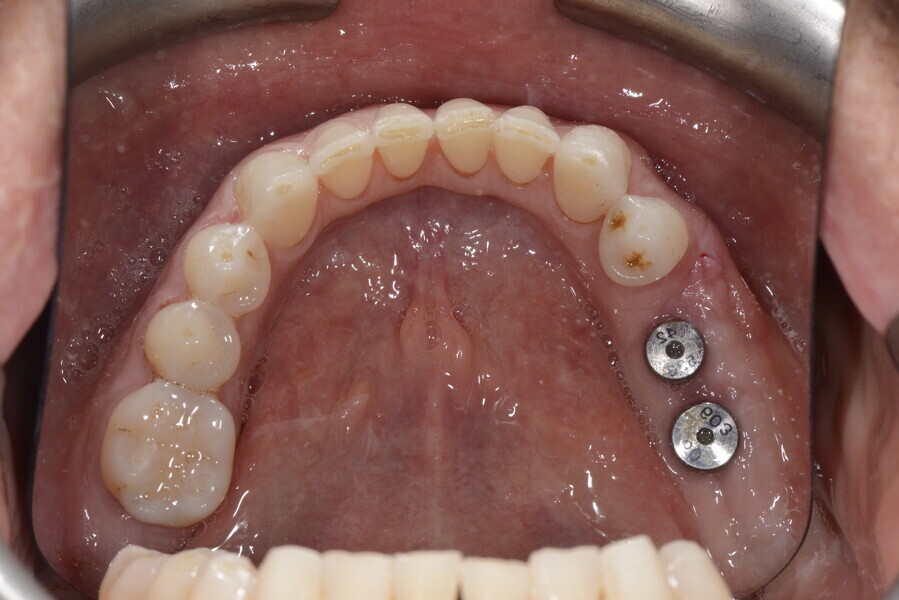

5. sinus lift for bone regeneration and implant placement with periodontal surgery where needed; and

6. ceramic veneers in the anterior area and crowns on the implants in the posterior area.

This patient, like all patients requiring interdisciplinary rehabilitation, had to first undergo periodontal treatment and caries restoration (Fig. 17). At the same time, it was important to rehabilitate swallowing with Froggymouth and relax the masticatory muscles and relieve the TMJs with an occlusal device. We could then study the orthodontic treatment plan using Invisalign ClinCheck (Align Technology) and showed the treatment plan to the interdisciplinary team and to the patient (Fig. 18). We were then able to create the correct sequence of orthodontic treatment, bone augmentation and implant surgery needed for the posterior edentulous spaces.

After the first phase of aligner treatment, we had achieved better inter-arch coherence, better maxillary arch expansion, and some space for improving the anterior tooth proportions restoratively (Fig. 19). We then temporarily restored the anterior teeth directly with composite, closing the spaces, improving the tooth proportions and further increasing the maxillary arch expansion (Fig. 20). We used restorative arch expansion to reduce the orthodontic destabilisation of the teeth to achieve the correct inter-arch coherence and retain the teeth in the cortical bone.38 A refinement aligner phase was undertaken to improve the final alignment of the gingival zenith and to improve the inter-arch coherence (Fig. 21). The periods of the first orthodontic phase and of the refinement were used to augment the mandibular and maxillary bone and to place the implants (Fig. 22). At the end of the orthodontic treatment, the case was finalised with ceramic veneers in the anterior area and temporary restorations on the implants in the posterior area (Figs. 23–26).